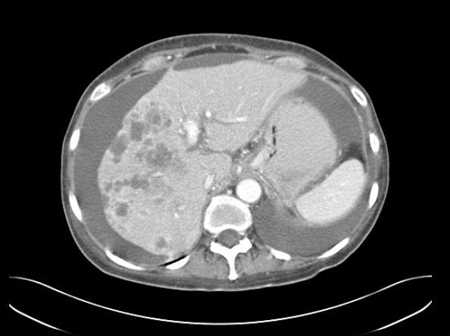

- TC do tórax/abdome/pelve

- tomografia por emissão de pósitrons com 18F-fluordesoxiglucose/TC (FDG-PET-TC)